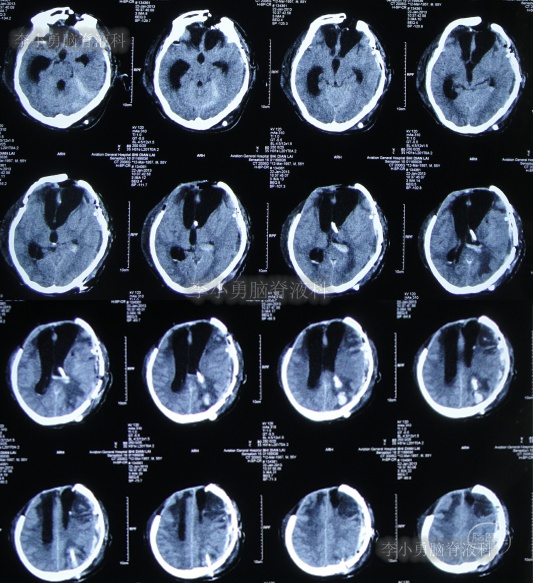

为求进一步治疗,2022年4月29日,第2次来李小勇脑脊液科治疗。入院时:意识不清,刺痛后四肢能动(图-31),查头颅CT(图-32)示脑室有扩张,有积气。

图-32:2022年4月29日头颅CT

入院后当天进行了原分流管拔除术+脑室引流术,术后当天查头颅CT示有出血(图-33)。

图-33:2022年4月29日术后头颅CT

术后5天即2022年5月3日,查头颅CT示脑室有缩小(图-35)。

图-35:2022年5月3日头颅CT

2022年5月13日(入院治疗15天),查头颅CT示脑室又有缩小(图-36)。

图-36:2022年5月13日头颅CT

2022年5月23日(入院治疗25天),查头颅CT示脑室缩小(图-37)。

图-37:2022年5月23日头颅CT

脑脊液化验变正常后于2022年9月9日(治疗133天),进行了脑室腹腔分流术(图-39)。

图-39:2022年9月9日头颅CT

2022年9月23日(李小勇脑脊液科治疗147天)出院,出院时:意识清楚,肢体活动、走路正常,住院期间脑脊液未见漏(图-40);出院前头颅CT示颅骨缺损(图-41)。

图-41:2022年9月19日出院前头颅CT